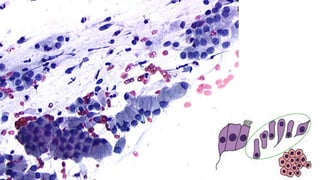

Citoplasma relativamente abundante, delicado,

semitransparente, que cora fracamente em azul, às vezes com

vacúolos.

Os núcleos são redondos ou ovais, com alguma variação do

tamanho, cromatina finamente granular exibindo cromocentros

ou nucléolo.

Quando as células são vistas lateralmente, assumem a forma

colunar alta característica, com núcleo oval, localizado na

região basal. Nessa perspectiva, quando em conjuntos,

constituem os arranjos conhecidos como “fila”, ou “paliçada”.

Quando as células são vistas de frente, elas se agrupam em

conjuntos monoestratificados, perdem a sua forma colunar e

apresentam, às vezes, bordas citoplasmáticas bem definidas,

lembrando um “favo de mel”. Os núcleos arredondados

mostram polaridade conservada (a distância entre os núcleos

é relativamente constante, não ocorrendo sobreposição

nuclear).